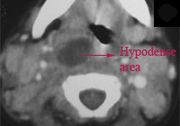

| 04:56, 23 October 2018 | Paramass mri.jpg (file) |  |

52 KB | Drtbalu | |